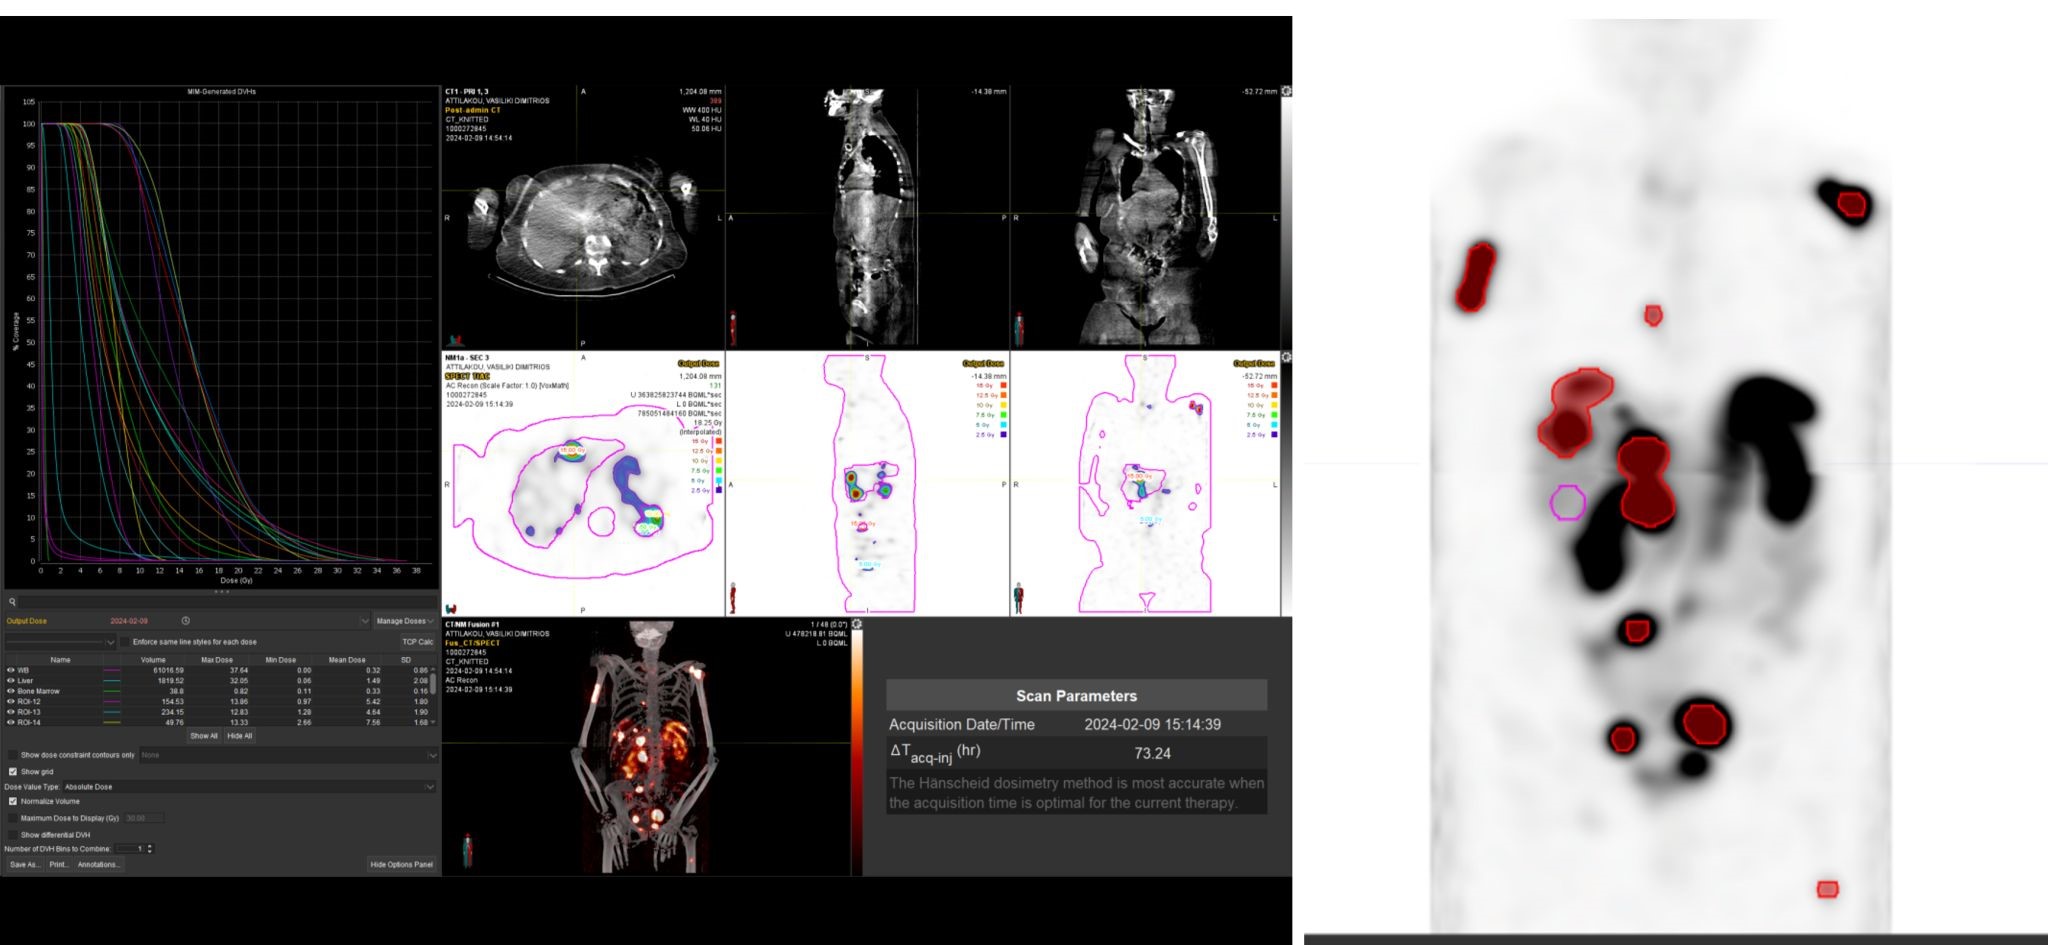

Ιδιαίτερα σημαντική είναι η χρήση των δεδομένων της PET/CT από το Κέντρο Ακτινοθεραπευτικής Ογκολογίας, για τον ακριβή σχεδιασμό της ακτινοθεραπείας, με στόχο την επίτευξη του καλύτερου θεραπευτικού αποτελέσματος και τη μικρότερη δυνατή ακτινική επιβάρυνση των υγιών ιστών.

Με τη χρήση ειδικού λογισμικού Τεχνητής Νοημοσύνης (MIM – Lesion ID) πραγματοποιείται αυτόματος υπολογισμός της έκτασης και του όγκου των θέσεων ενεργού νόσου. Ξεπερνώντας τις δυνατότητες του ανθρώπινου οφθαλμού υπολογίζεται το συνολικό φορτίο νόσου πριν και μετά την θεραπεία επιτρέποντας ακριβέστερο χειρισμό του ασθενούς από τον θεράποντα ιατρό.

Η αξία της μεταθεραπευτικής δοσιμετρίας

Με τη SPECT‑CT ποσοτικοποίηση υπολογίζουμε απορροφούμενες δόσεις σε όγκους και όργανα‑στόχους (νεφροί, σιελογόνοι, ήπαρ, μυελός κ.ά.). Αυτό:

Σημείωση: Σύμφωνα με πρόσφατες κλινικές εργασίες/σειρές ασθενών – όπως οι LUMEN‑2 (για ΝΕΤ) και νεότερες μελέτες σε PSMA‑στόχο – η ποσοτική δοσιμετρία συσχετίζεται με την έκβαση και βελτιώνει τον θεραπευτικό σχεδιασμό.

Με βάση τα σύγχρονα Guidelines όλων των διεθνών ογκολογικών εταιρειών η μεταθεραπευτική απεικόνιση είναι προαπαιτούμενο για την έναρξη-συνέχιση της θεραπείας και το βέλτιστο αποτέλεσμα αυτής.